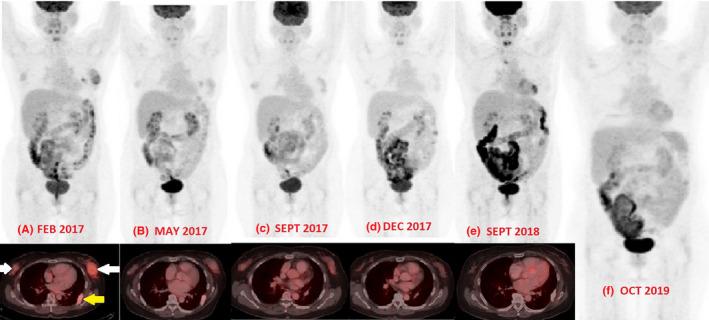

Relapsed plasmablastic lymphoma in a HIV-negative patient: Pushing the envelope.

This case emphasizes that, with the availability of novel immunotherapy agents (Daratumumab), and repurposed use of bortezomib, a patient with HIV-negative relapsed PBL can be treated successfully and consolidated with an allogeneic haploidentical hematopoietic cell transplantation.